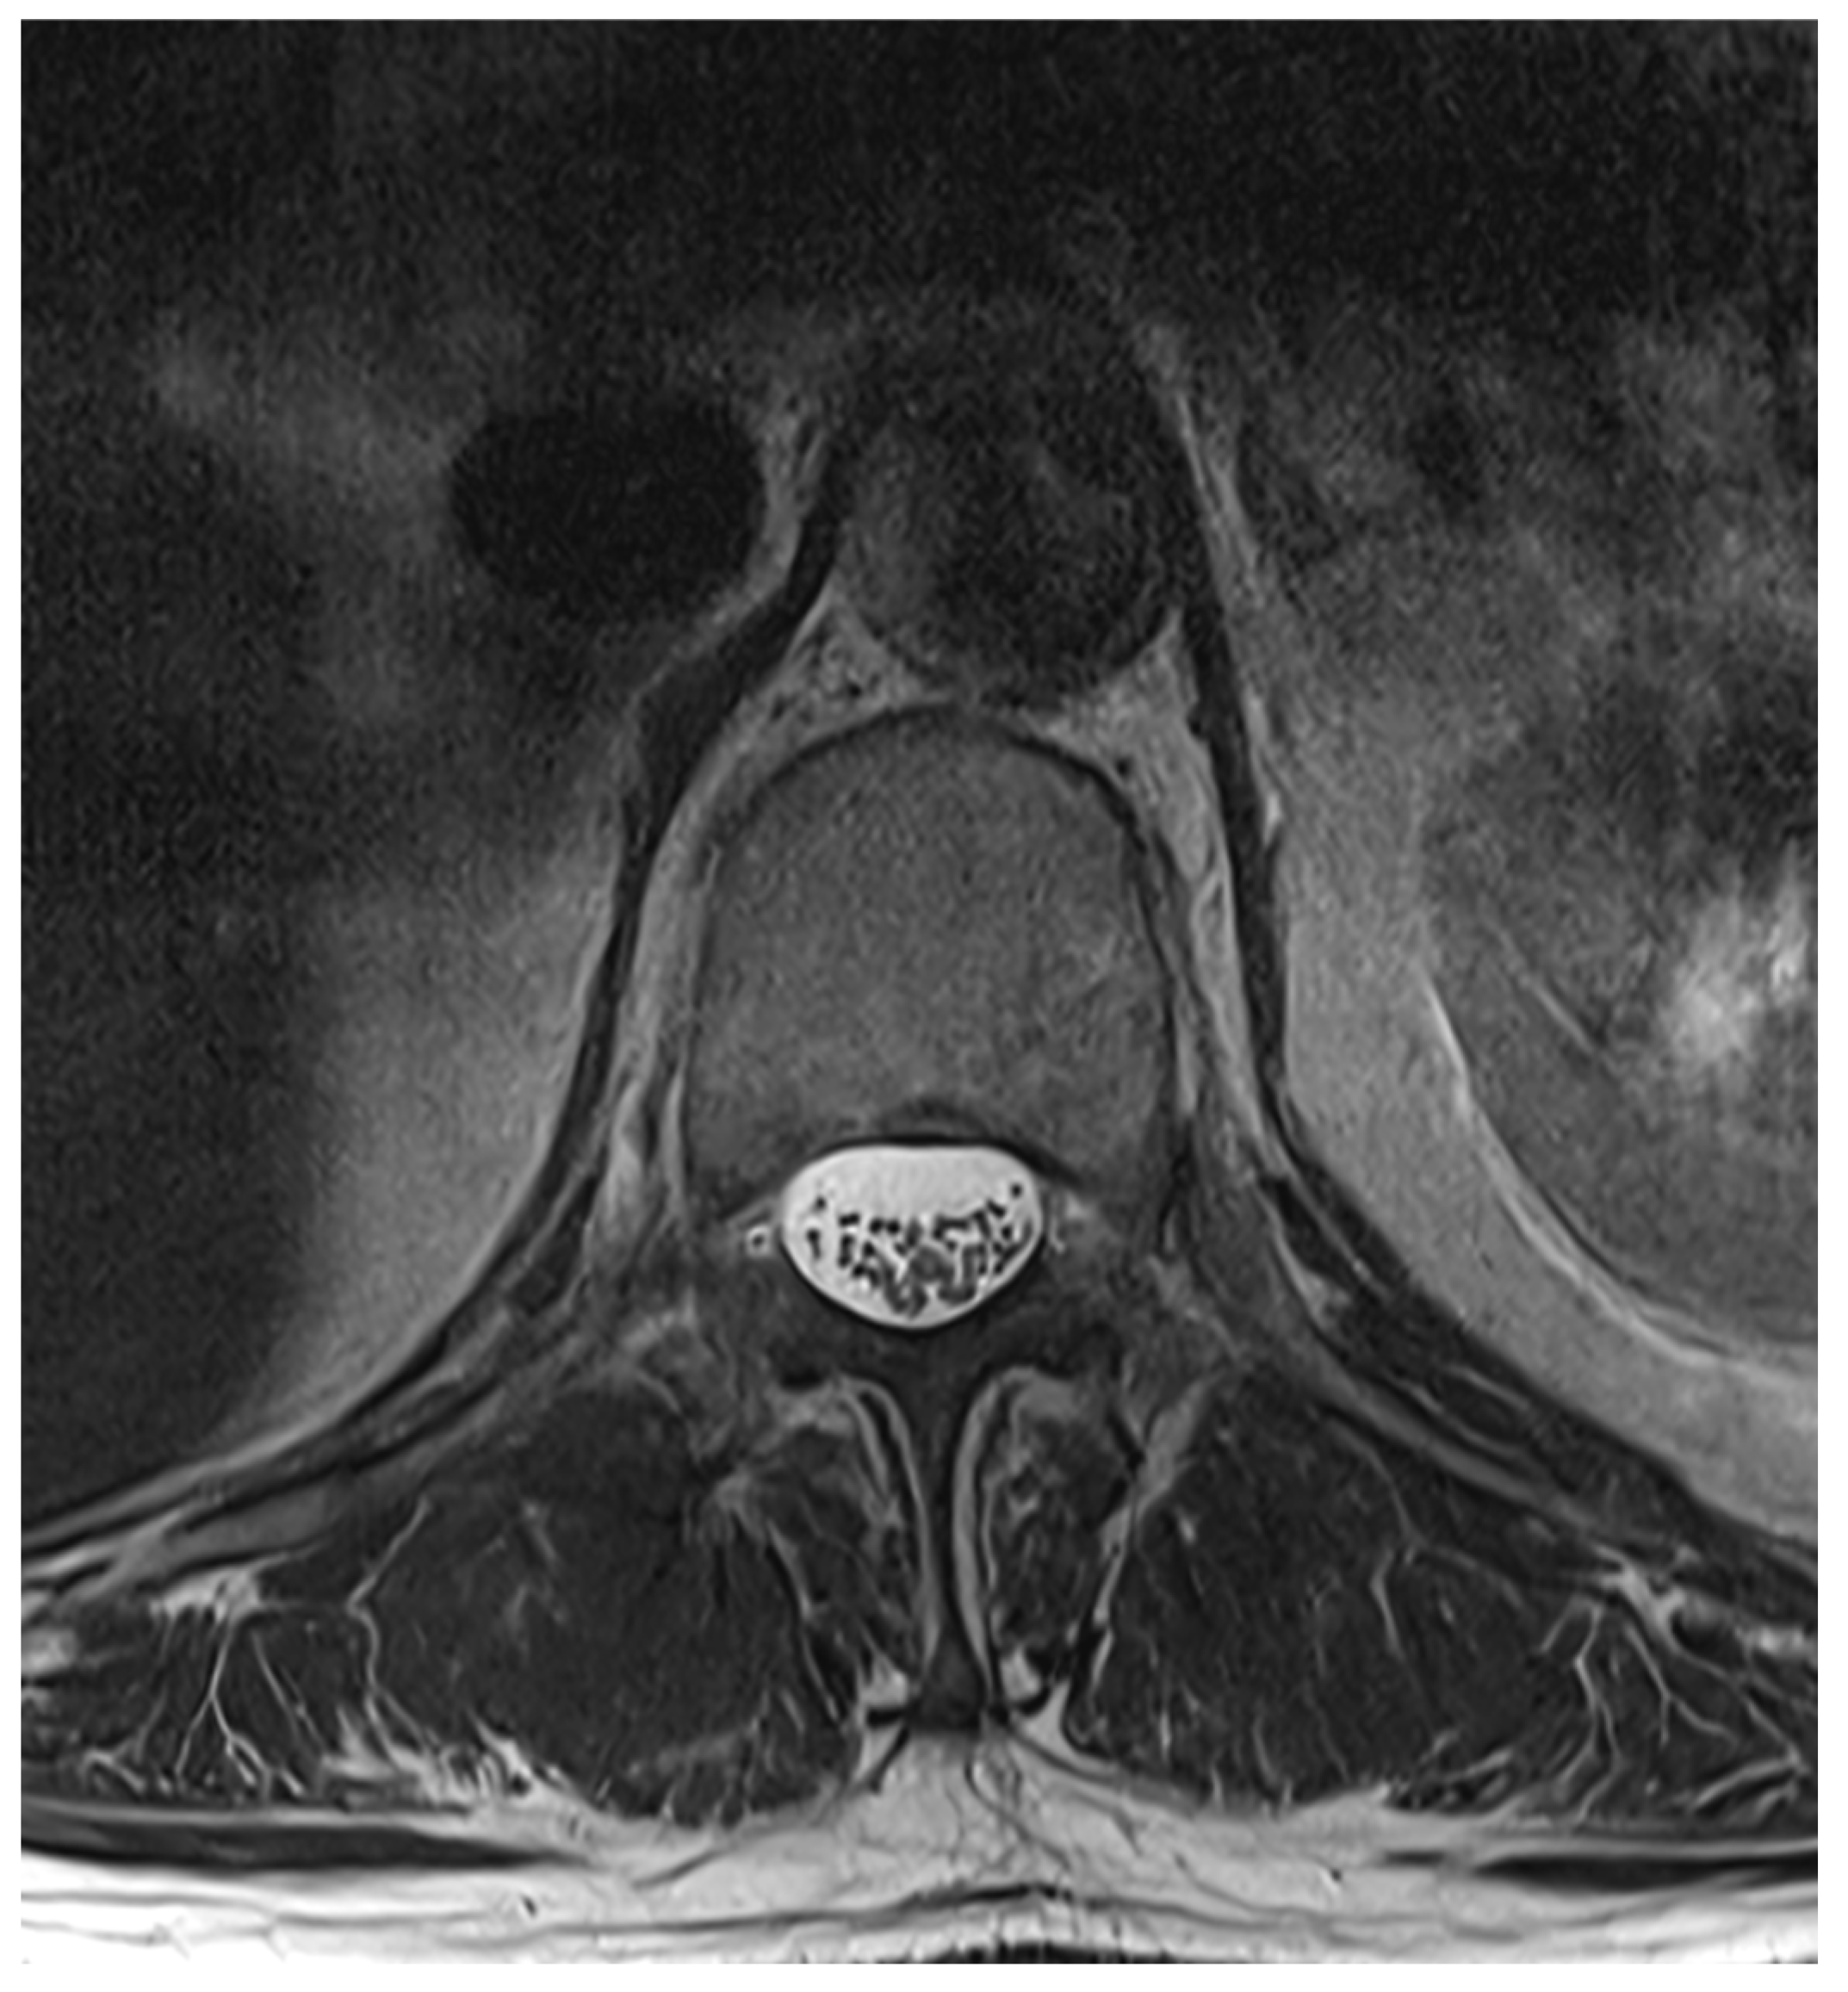

Among the 722 punctures, complications occurred in four cases (0.6%), see Table 3. Three of these complications arose after the first administration and one after the second. Reported complications included one case of post-puncture aggravation of pain, and one case of post-puncture headache. Both cases were managed conservatively using analgesics. In one case, shortness of breath occurred. In this patient, a cardiopulmonary event was ruled out, which required performing blood sampling as well as a CT-angiography of the pulmonary arteries. In another case, an intracranial subdural hygroma occurred, see Figure 2. No neurological deficits occurred, but due to persistent headache, an MRI scan was performed which revealed the diagnosis. The patient was readmitted for inpatient treatment for another 5 days 1 month after initial puncture. An MRI scan of the lumbar scan revealed epidural accumulations of cerebrospinal fluid at the thoracolumbar junction (Figure 3). Bed rest was ordered for 3 days. 2 days after readmission, a CT-guided lumbar blood patch was performed at the level L2 with 35 mL of blood, and oral analgesics were administered. The patient was discharged after five days. At subsequent follow-up visits, the patient reported no further headaches, and an MRI performed six weeks later demonstrated the complete resolution of the epidural cerebrospinal fluid collections (Figure 4).

Figure 3. Axial T2-weighted MRI at L1, showing epidural cerebrospinal fluid accumulation both ventral and dorsal to the thecal sac.